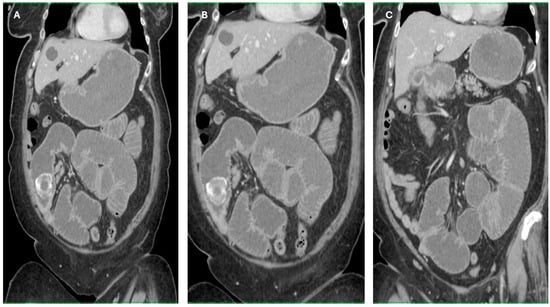

Imaging findings were consistent with biliary ileus, characterized by the presence of ectopic gallstones within the gastrointestinal tract. As shown in Figure 3A–C, axial and coronal CT images demonstrated radiopaque enteric gallstones. Figure 4 highlights a gallstone associated with a cholecystoduodenal fistula. Further axial and coronal sections (Figure 5A–C) show additional enteric gallstones, including one in the rectal ampulla.

Figure 4. Enteric gallstone associated with cholecystoduodenal fistula. Coronal reconstructed CT images showing an ectopic gallstone within the intestine, secondary to a cholecystoduodenal fistula—a classic radiological finding in biliary ileus. (AC) Coronal reconstructions showing multiple distended small bowel loops upstream from the obstruction site, with the intraluminal gallstone visible in the terminal ileum. Acquisition with 5 mm slice thickness and 3 mm reconstruction. Images have been cropped and zoomed for optimal visualization while maintaining the original scale; a 10 mm scale bar is included in each panel.